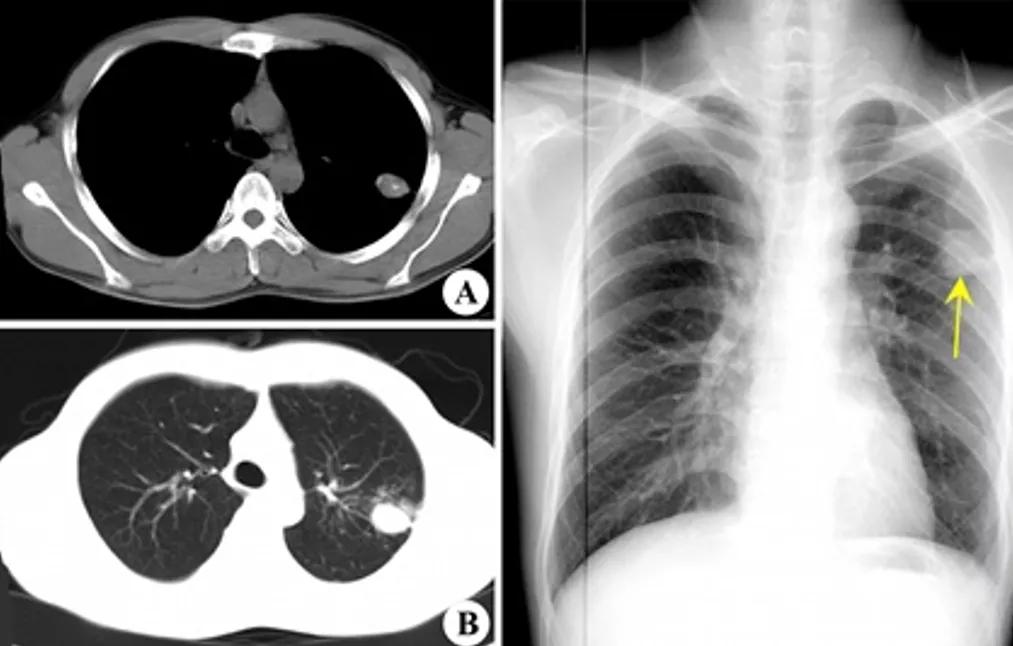

图:2017-1 胸部CT:左肺上叶后段团片影,较前片有所减小;两肺多发炎症,较前片部分吸收;右侧胸膜增厚、胸腔积液,较前片有所增多。

病例2:

男性,42岁。 2008年诊断干燥综合症,当时胸部影像学未见异常。糖皮质激素30毫克/日 ,减量过程中口干症状加重,2009年7月再次全身检查,胸部CT见左上肺尖段软组织影,伴空腔。(似乎存在空洞,有些低密度区,但究竟是不是空洞呢?需要进一步确认。)

病灶穿刺病理:肉芽肿性炎伴坏死,抗酸染色+。

抗痨治疗6月后: